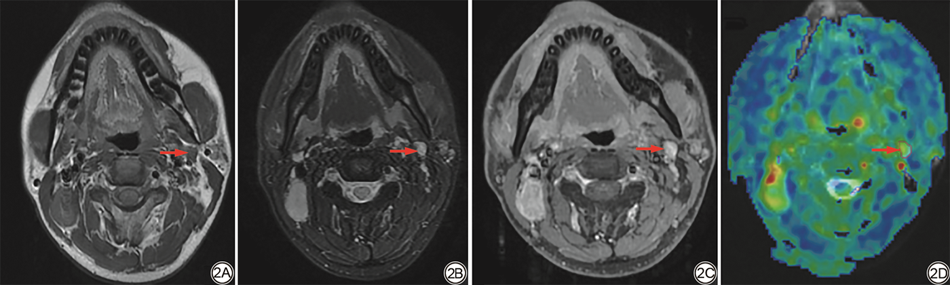

图2  男,30岁,鼻咽非角化性未分化型癌,Ⅲ期(T3N1M0),左侧颈部Ⅱ区SMLN(红箭)。2A:T1WI;2B:T2WI;2C:T1WI增强,2D:ASL/T2WI-FS 融合图,SMLN的ROI由红圈标示,其中颜色编码显示BF值的相对高低,黄色表示中等BF值区,绿色表示稍低BF值区,ROI内BFavg、BFmin、BFmax分别为55.5 mL/(min·100 g)、28 mL/(min·100 g)、83 mL/(min·100 g)。SMLN:小淋巴结转移瘤;ASL:动脉自旋标记;ROI:感兴趣区;BF:血流量;BFavg:血流量均值;BFmin:血流量最小值;BFmax:血流量最大值。

Fig. 2  A 30-year-old male with stage Ⅲ (T3N1M0) undifferentiated non-keratinizing of the nasopharynx carcinoma, exhibiting a left cervical level Ⅱ SMLN as indicated by the red arrow. The sequences are T1WI (2A), T2WI (2B), T1WI with enhancement (2C), and an ASL/T2WI-FS fusion image (2D). The ROI of SMLN is marked by a red circle, with color coding indicating the relative levels of BF values, where yellow represents medium BF value areas, and green indicates slightly lower BF value areas. The BFavg, BFmin, and BFmax within the ROI are 55.5 mL/(min·100 g), 28 mL/(min·100 g), and 83 mL/(min·100 g), respectively. SMLN: small metastatic lymph node; ASL: arterial spin labeling; ROI: region of interest; BF: blood flow; BFavg: average blood flow; BFmin: minimum blood flow; BFmax: maximum blood flow.